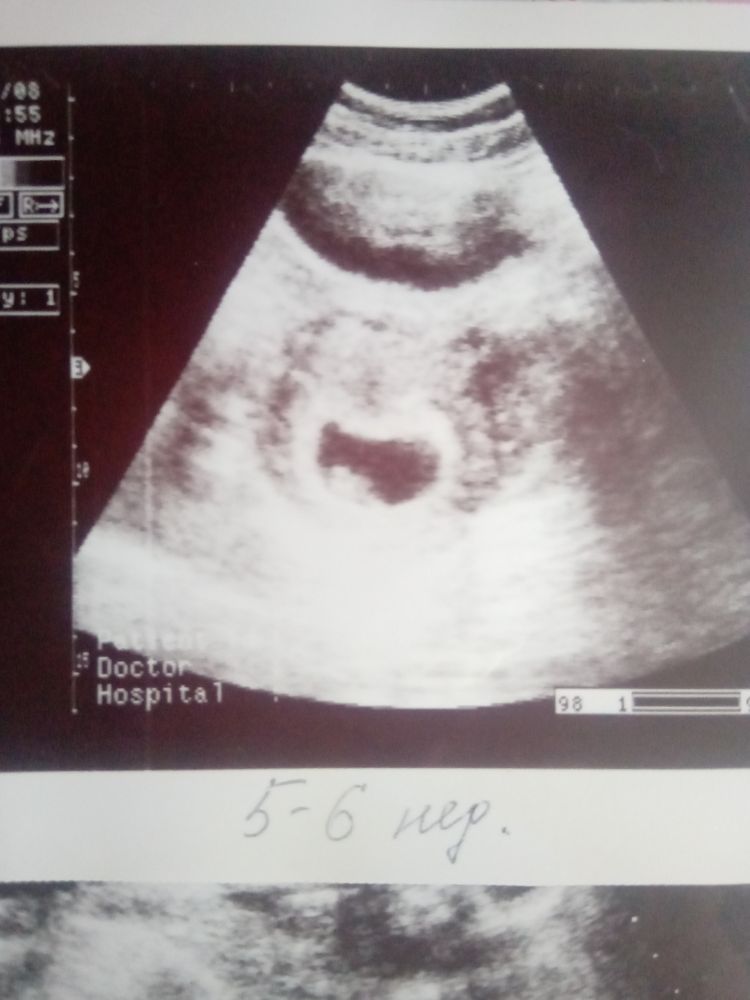

В 8 недель хороший такой уже эмбриончик. Вот узи со второй дочкой, срок 5-6 недель. Эмбрион, сб+

Но! Подождите обязательно, если говорят, что еще неделю, то надейтесь! Чудеса случаются 💕